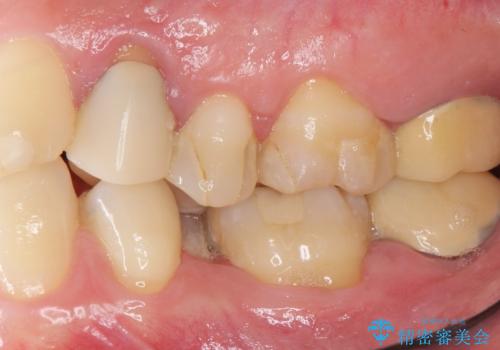

精査したところ、左下の小臼歯(左下5)が舌側転位しており、また隣の歯の詰め物は欠け虫歯になっていました。

矯正は絶対にしたくないという強いご希望により、舌側転位している歯を抜去し歯肉の治癒を待ったのち、両隣の歯の補綴治療を行いました。